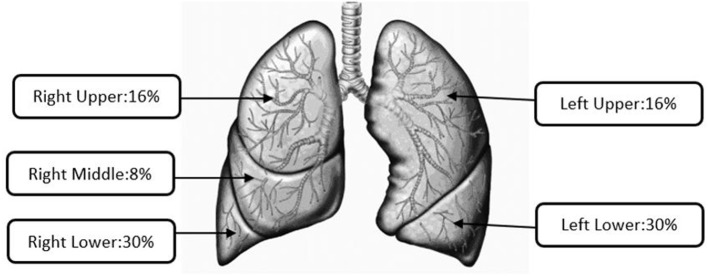

Unlike regional deposition, Yeh–Schum lobular deposition pattern characterized the segmental bronchi within each lobe as a single symmetric path to report the mass deposited in each of the five lobes of the human lungs: right upper (RU), right middle (RM), right lower (RL), left upper (LU), and left lower (LL) (ref. 36). The total lobar deposition includes deposition in the TB and pulmonary regions of each lung lobe but not the initial airways as they do not belong to any lobe. Default parameters for Yeh–Schum model were as follows: forced residual capacity = 3,300 ml, upper respiratory tract volume = 50 ml, breaths per minute (bpm) = 12, and tidal volume = 625 ml.

Figure 3 presents the average lobular aerosol mass depositions of all the studied e-liquids. However, higher percentages of the aerosol mass were found to be deposited in right-sided lung lobes (RU, RM, and RL = 54%) compared with the left-sided lung lobes (LU and LL = 46%). Manigrasso et al. have presented right lung lobes as the sites where effects of the EVP aerosol occur more likely than left lung lobes (ref. 39). The highest percentages of lobular deposition of emitted aerosols from all the oils were predicted in the lower lobes (right: 30 ± 0.2% and left: 30 ± 0.2%) compared to other lobes of the lungs (RU 16 ± 0.2%; RM 8 ± 0.1%; and LU 16 ± 0.2%). For particle sizes in the range from 0.2 to 1 μm, higher deposition fractions in lower lobes compared to the upper lobes were also documented, as observed in our results and prior studies (ref. 36, ref. 40–ref. 43).

Out of the total respiratory tract deposition for all the diluent oils, the highest fraction (~0.08–0.11) and mass per puff (mg/puff: 0.04–0.21) were predicted in the pulmonary region where gas exchange occurs. Lewis et al. (ref. 29) noted that a maximum probability of particle deposition in the pulmonary region was for particles with MMAD <3 μm and GSD <3. For smaller-sized particles with MMAD <2 μm, Raabe et al. (ref. 47) concluded that the highest fraction of total deposited particles is reported in the pulmonary region. Dosimetry results presented in this study for VEA were consistent with these inhalation toxicological evaluations. We observed that VEA resulted in the highest total mass collected (5.60 mg) via cascade impactors and the highest total respiratory tract deposition (~0.26) via dosimetry analysis, compared with all the e-liquids included in the study. Literature showed the higher lobular depositions of submicron size particles in lower lobes than upper lobes of the lungs (ref. 36, ref. 40–ref. 43), which is the same as our study results. Using number concentrations, Manigrasso et al. estimated size-segregated aerosols emitted from commercially available EVP as a function of the airway generation number in the lung lobes. They concluded that, for both the TB and pulmonary regions, twice as many particles were deposited in RU compared to the LU and ~0.20 more particles deposited in RL compared to LL. Cumulatively, right lung and lobar bronchi were documented as sites where PG–VG-based e-liquid aerosols may likely affect more than the left lung, which is consistent with our study results.

Dosimetry analysis predicted that ~60% of total respiratory depositions of particles were in the pulmonary (~42%) and TB (~20%) regions for VEA. Irrespective of statistical difference in their size distribution, aerosolized particles were predominantly (~69% or more) deposited in lower lobes (Right: ~30% and Left: ~30%) of the lungs. These observed particle deposition patterns were consistent with previous inhalation toxicological studies and with characterization of BALF of EVALI cases, which support the pulmonary region of the lung as the site of injury. The study results presented herein help to explain existing clinical presentations and pathological findings by providing particle size distribution of diluent oils and their respiratory depositions. Additionally, EVP aerosol sizes less than 1 μm, which have high probability of being inhaled then exhaled, could pose secondhand exposure risk to persons in proximity to EVP users in occupational and non-occupational settings. While elimination of VEA in e-liquid products seemed to mitigate the EVALI outbreak, further research is required to investigate the usage of other commonly available oil diluents in Δ9-THC-based e-liquid preparations, which could also be potentially harmful for users and bystanders.